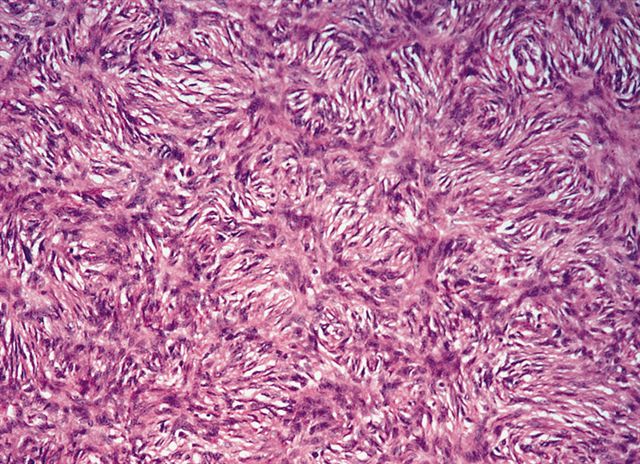

- Low grade dedifferentiated liposarcoma

- Less common low grade tumor resembling fibromatosis or well differentiated fibrosarcoma

- Nonlipogenic (in contrast to well differentiated spindle cell liposarcoma, which contains atypical fat / lipoblasts)

- Considered by some to be the same as cellular atypical lipomatous tumor, although there is evidence that even low grade dedifferentiation is associated with a poorer prognosis when compared with conventional atypical lipomatous tumor

- Now a recognized WHO classification

Microscopic (histologic) images

Contributed by Michael R. Clay, M.D. and AFIP